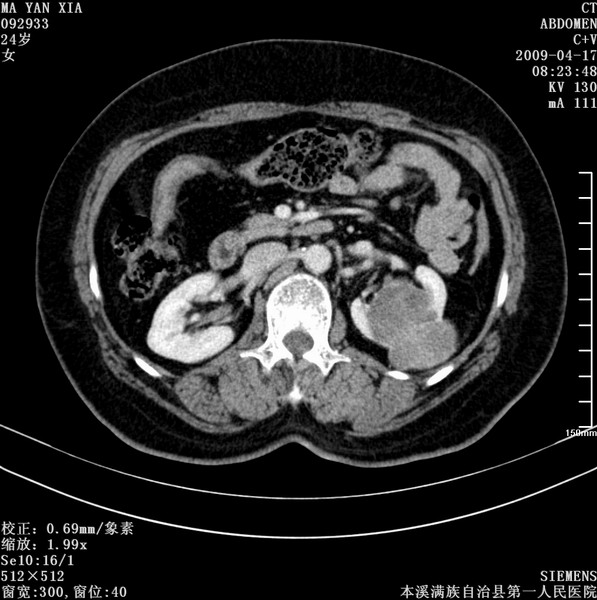

标题: CT19443:肾脏肿瘤两个区强化不一样。 [打印本页]

标题: CT19443:肾脏肿瘤两个区强化不一样。

女,51岁,体检时发现肾脏占位,建议ct增强。无任何自觉症状。

典型的不均匀强化,左肾癌